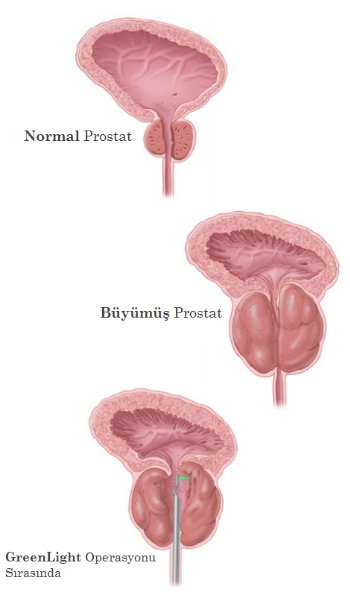

GreenLight Lazer terapisi nedir?

Lazerler, sağlıkta birçok alanda kullanılmaktadır, bunlar kozmetik ve göz ameliyatları gibidir. Ayrıca iyi huylu prostat büyümesinde de kullanılırlar.

GreenLight operasyonu sırasında, üretrayı bloke eden doku hızla ısıtılır ve hücreler su içerdiğinden genişler ve buharlaşırlar. Normal idrar akışı eski haline hızlı bir şekilde geri döner.

GreenLight operasyonu sırasında ne olur?

- Anestezi vücuda etki ettikten sonra, doktor üretranızdan küçük bir kamera yardımı ile giriş yapar ve üretra, prostat ve mesanenizin iç yüzeyini görüp, inceler.

- Daha sonra kamera yardımı ile GreenLight fiber optiği işlem yerine kadar ilerletir.

- Doktor idrar akışını engelleyen prostat dokusunu buharlaştıracaktır. Hemen buharlaşmayan bazı ölü dokular, ameliyatınızdan sonraki birkaç gün içerisinde idrar yolu ile atılacaktır.

Prostat Görüntüsü